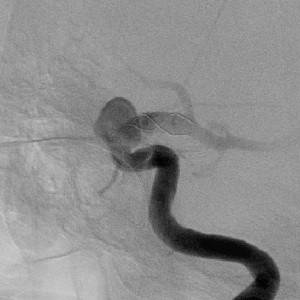

(1) DSA leve unutrašnje karotidne arterije (ACI), pokazuje kompleksnu aneurizmu na C5 segmentu

(2) 3D DSA leve ACI

(3) Implantacija stenta (DSA druga projekcija)

(4) Aneurizma isključena iz cirkulacije koilima

(DSA nakon embolizacije)